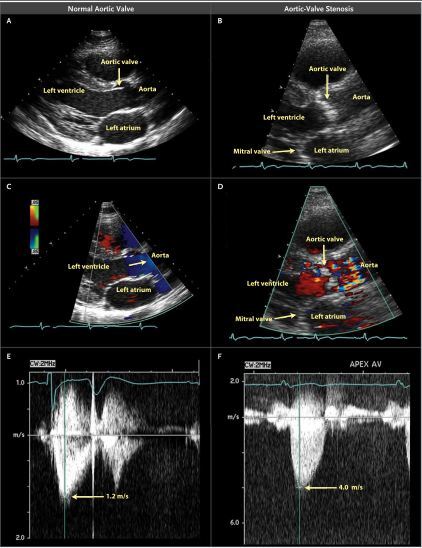

2019-03-14 09:30 205 主动脉瓣狭窄 心力衰竭 TAVR 外科主动脉瓣膜置换 最新资讯 华法林 多巴酚丁胺 凝血酶 临床综述 cardio2014 心血管频道2014年度专题 专题title文章

编者按本文为Otto博士和Prendergast博士发表在2014年8月21日的NEJM杂志上的一篇关于主动脉瓣狭窄的文章,文章从疾病危险因素、预防